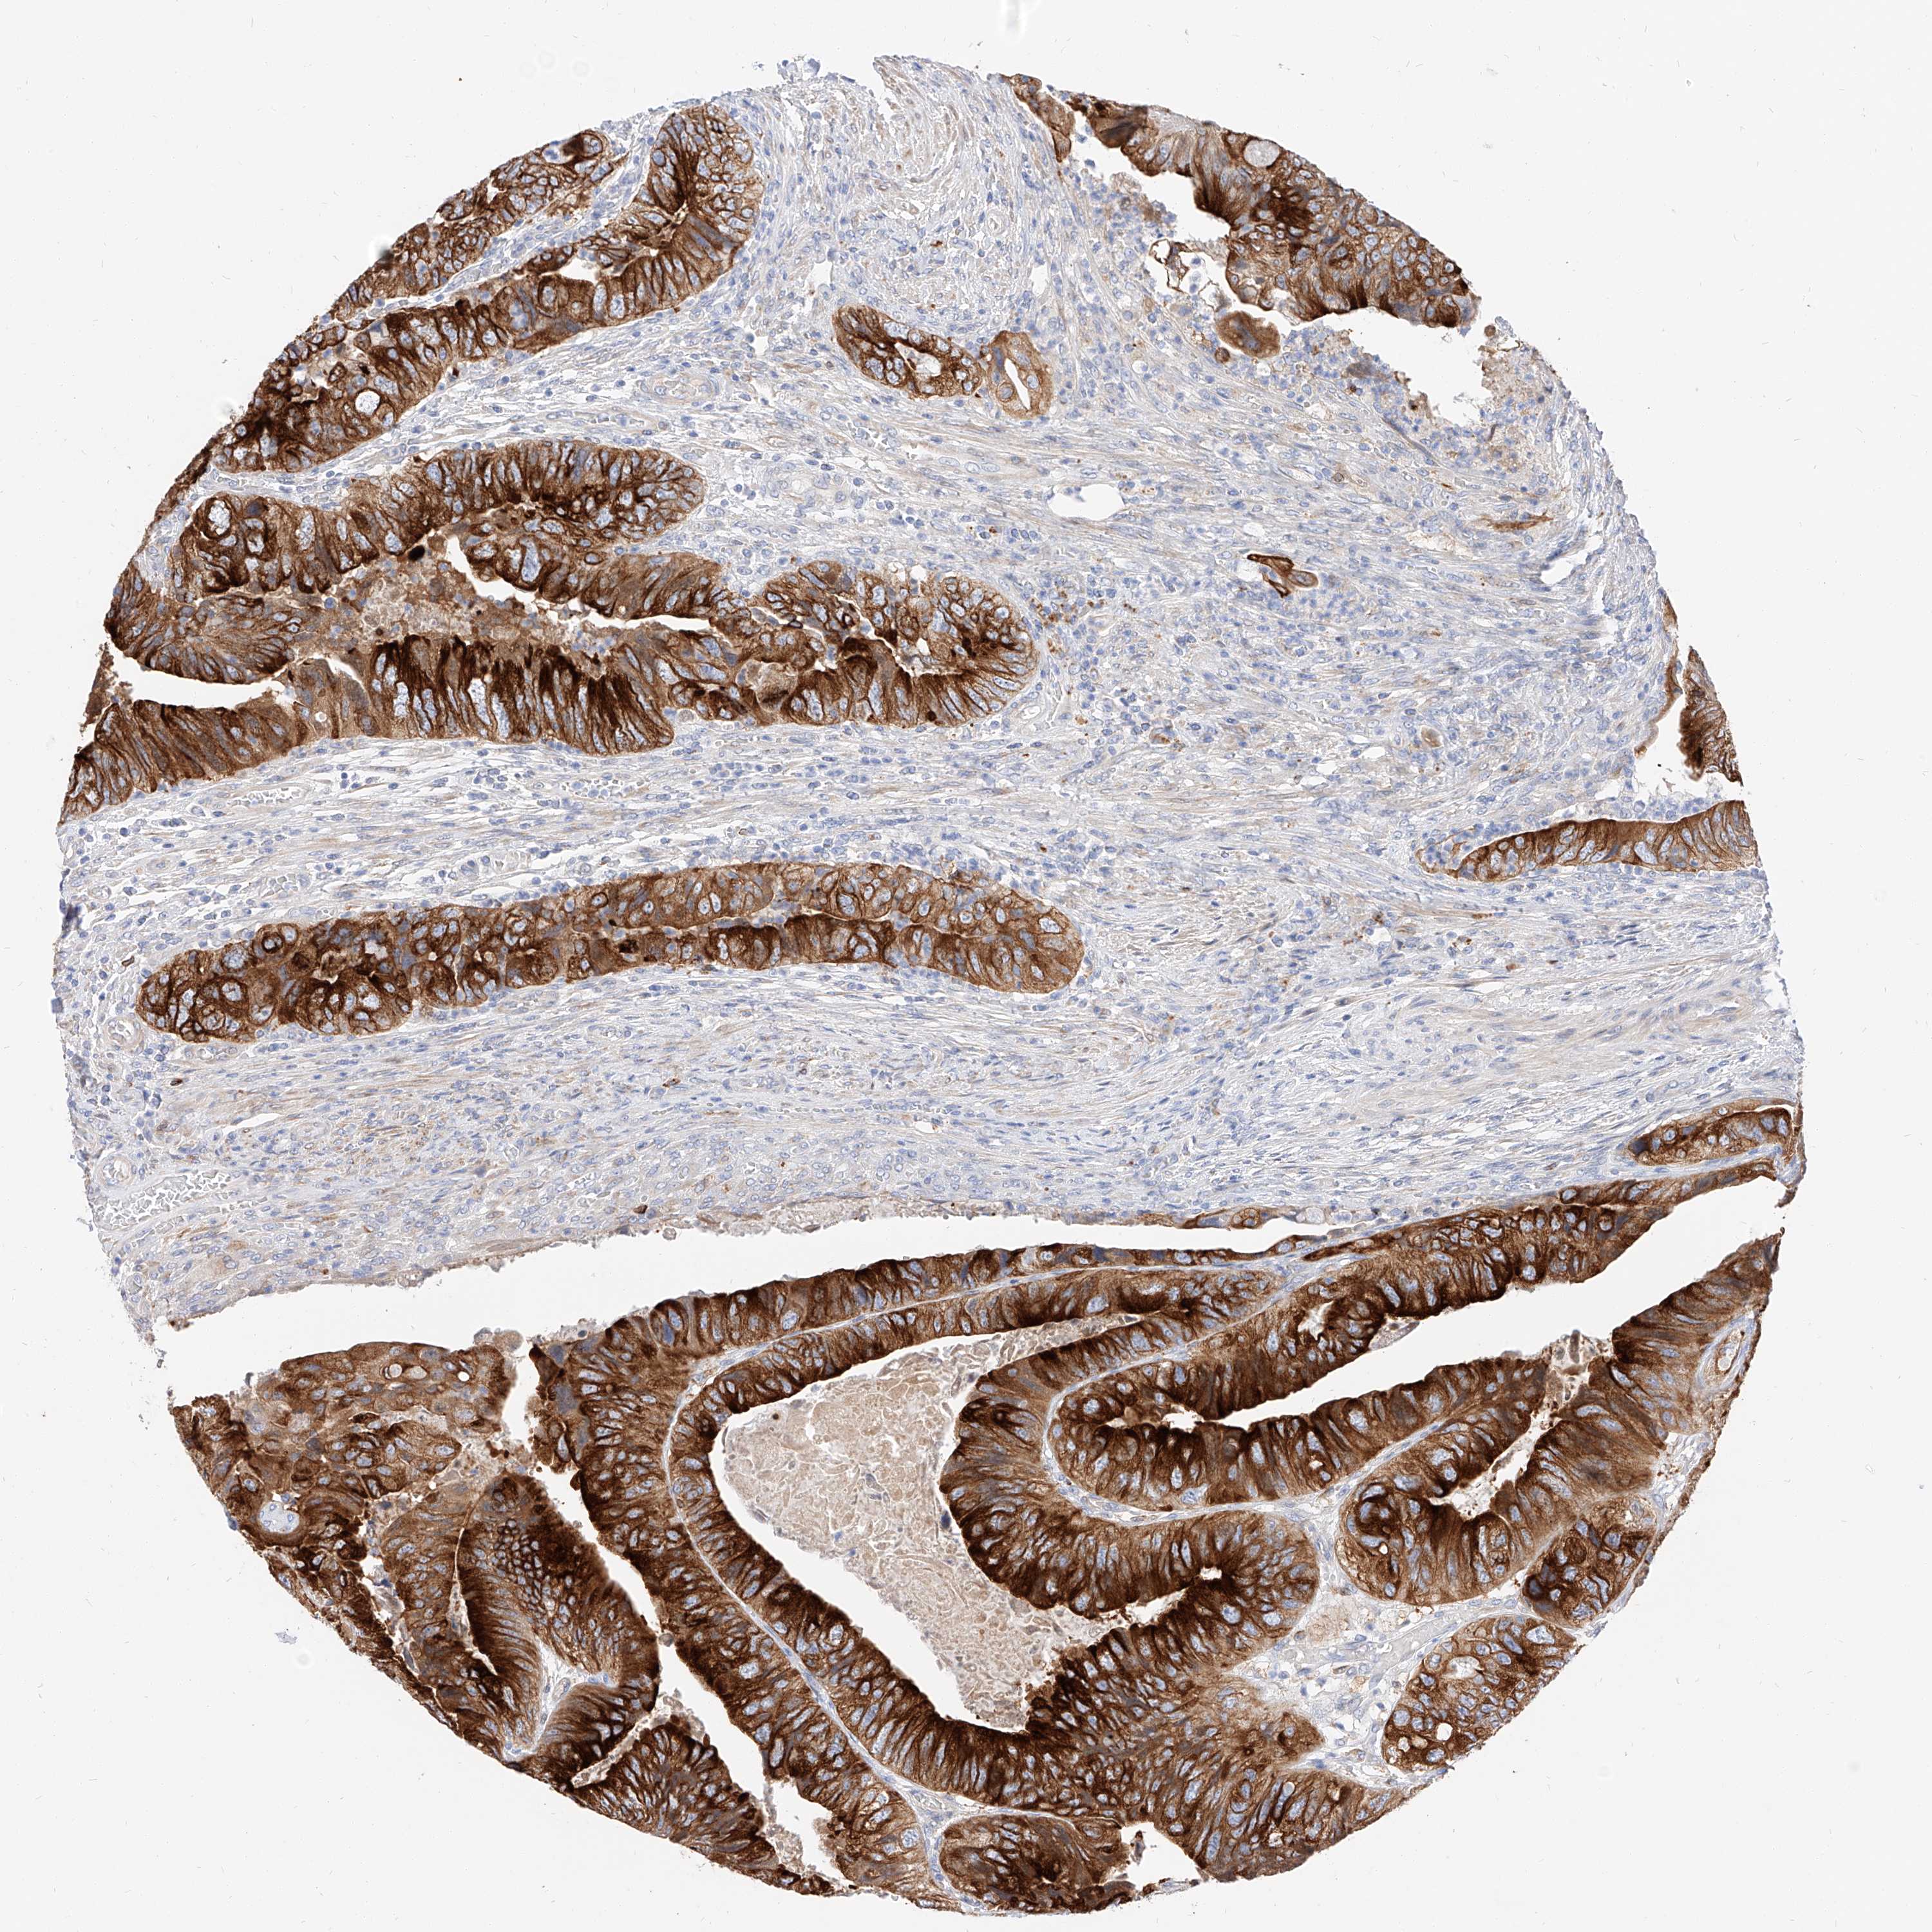

CANCER COLORECTAL CANCER Show tissue menu

Colorectal cancer

Human cancer

Colon adenocarcinoma